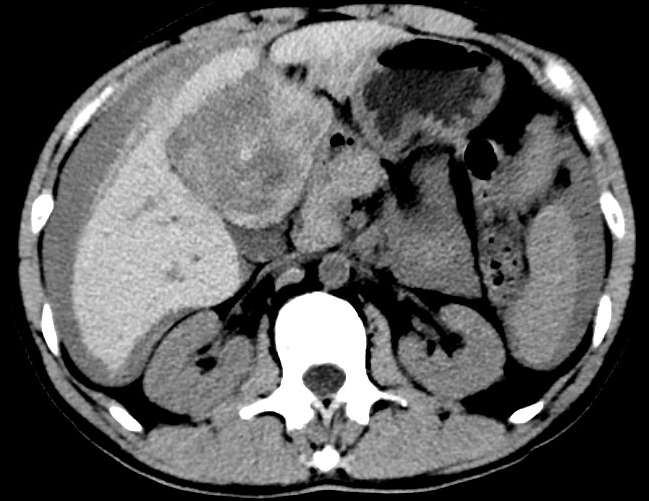

放下電話的白葦急赴消內(nèi)三搶救室會(huì)診,經(jīng)仔細(xì)查體、對(duì)患者腹部CT進(jìn)行詳細(xì)閱片、綜合評(píng)估患者后,考慮患者是肝占位破裂出血?;颊卟∏槭志o急、一刻也不容耽誤,需立刻急診行肝動(dòng)脈造影 栓塞術(shù)進(jìn)行止血治療,在與患者家屬溝通后,立即通知消化介入室準(zhǔn)備急診手術(shù)。

入手術(shù)室時(shí),患者神志迷糊,口唇干燥、重度貧血貌,心電監(jiān)護(hù)提示:心率140-160次/分,血壓70/43mmHg,這是失血性休克的表現(xiàn)!白葦快速建立靜脈通道緊急給予輸血,升壓,止血等液,立即給予肝動(dòng)脈造影,術(shù)中發(fā)現(xiàn)肝左葉疑似腫瘤病灶、病灶周圍血管分支有造影劑外溢,考慮血管破裂出血,迅速給予栓塞微球進(jìn)行肝動(dòng)脈栓塞。整個(gè)手術(shù)過(guò)程不足20分鐘,術(shù)后即刻患者心率降至100-110次/分、血壓升至90/60mmHg。

術(shù)后給予積極抗炎,止血,保肝、利尿等對(duì)癥治療,復(fù)查血常規(guī)提示活動(dòng)性出血停止后,在超聲引導(dǎo)下行腹腔穿刺引流術(shù),術(shù)后3天共引流出血性腹水約4000ml。患者經(jīng)復(fù)查各項(xiàng)指標(biāo)均趨于正常,復(fù)查CT提示腹腔積血已基本吸收,患者康復(fù)出院。